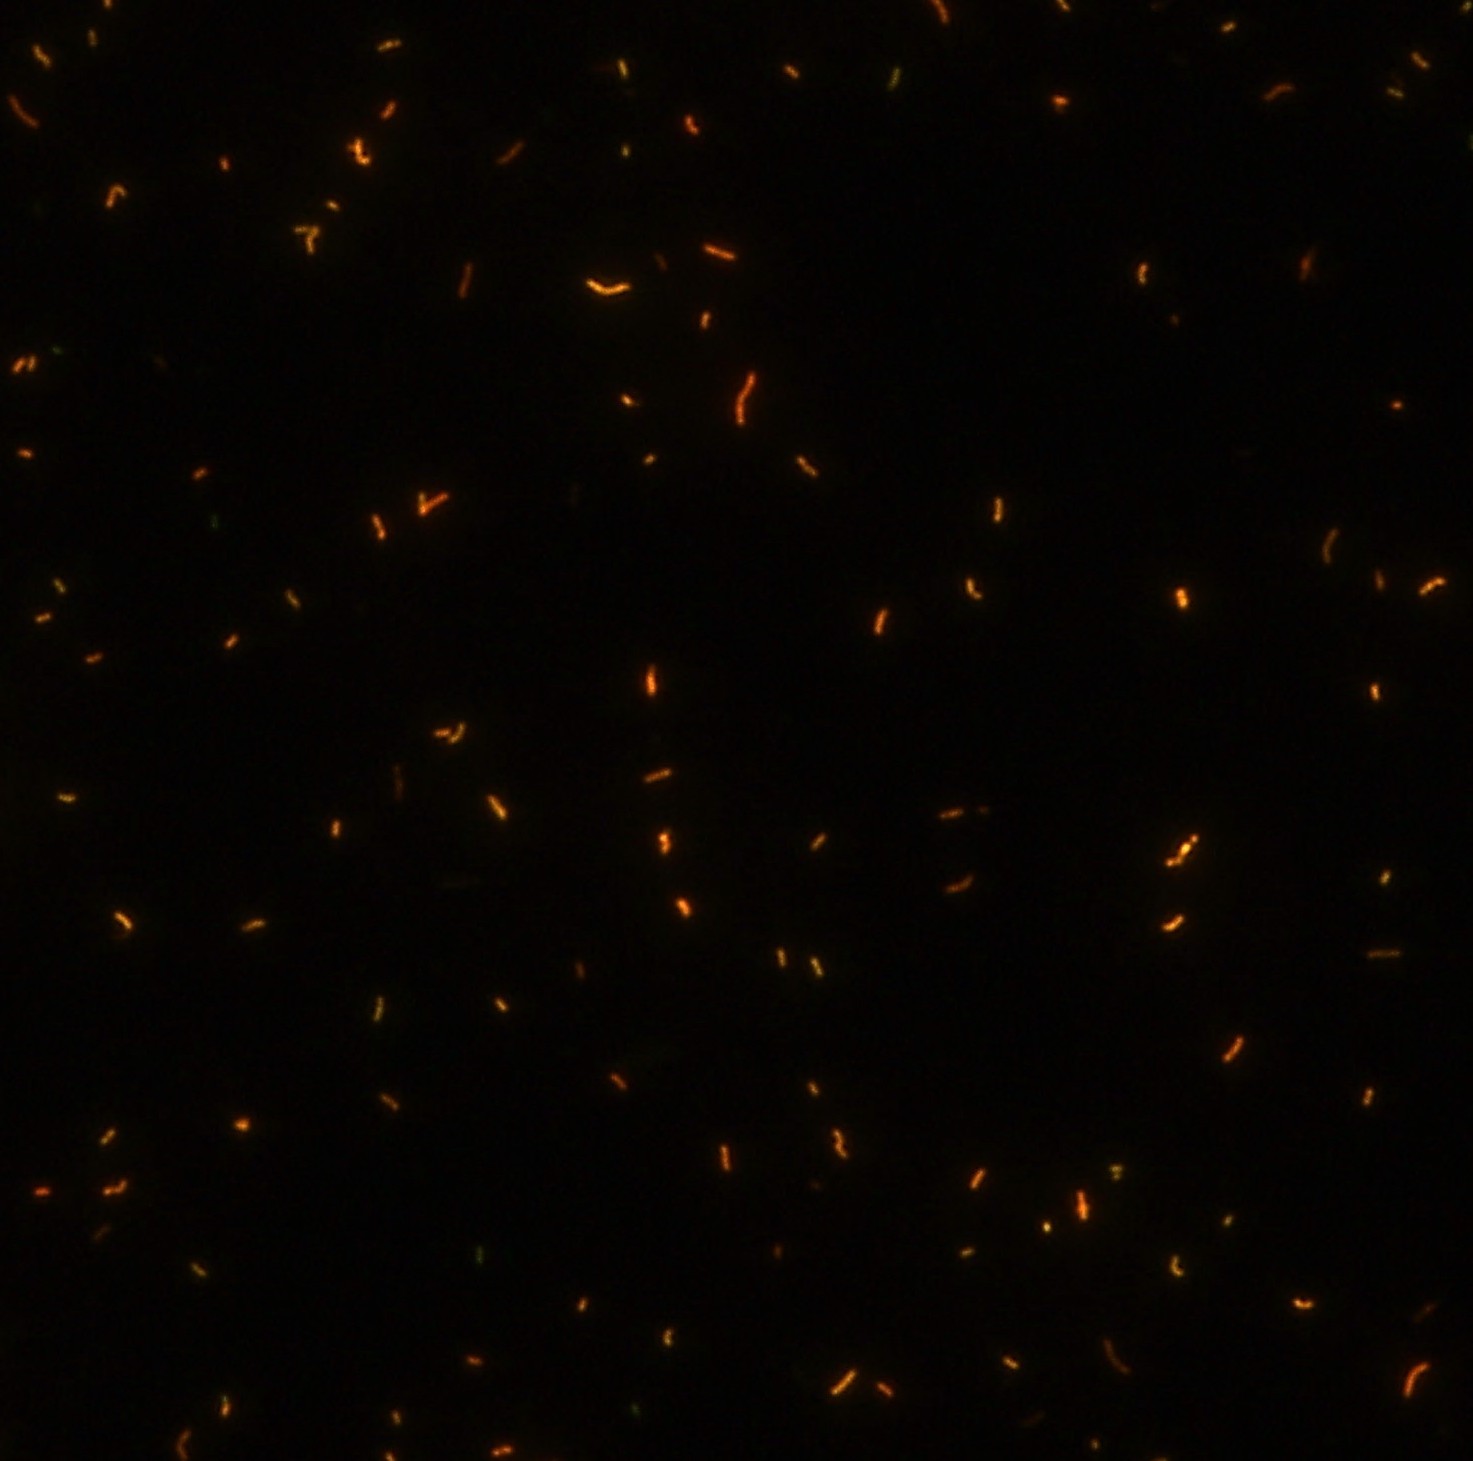

顯微染色技術是檢測結核桿菌方法之一。分枝桿菌細胞壁中含有分枝菌酸,其可以與染料牢固結合,具有“抗酸性”的特征。熒光染料金胺-羅丹明在染色中與抗酸生物細胞壁內(nèi)的分枝菌酸相結合,并耐受酸醇(脫色劑)清洗脫色。反染色劑高錳酸鉀被用來顯出染色生物。AFB(熒光)染色試劑盒設計既可用于自動染色機,也可用于手工染色。產(chǎn)品穩(wěn)定性好,染色效果佳。

染色結果 (熒光法×400)

用于分枝桿菌、諾卡菌等細菌抗酸染色,包括熒光染色。